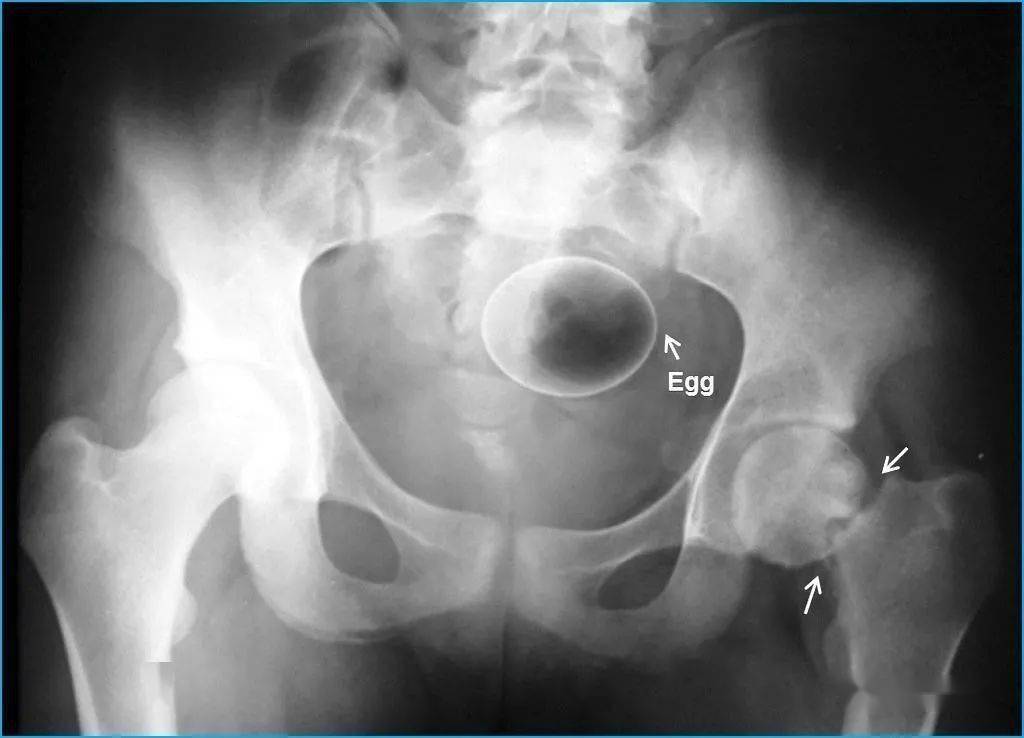

▷两个鸡蛋